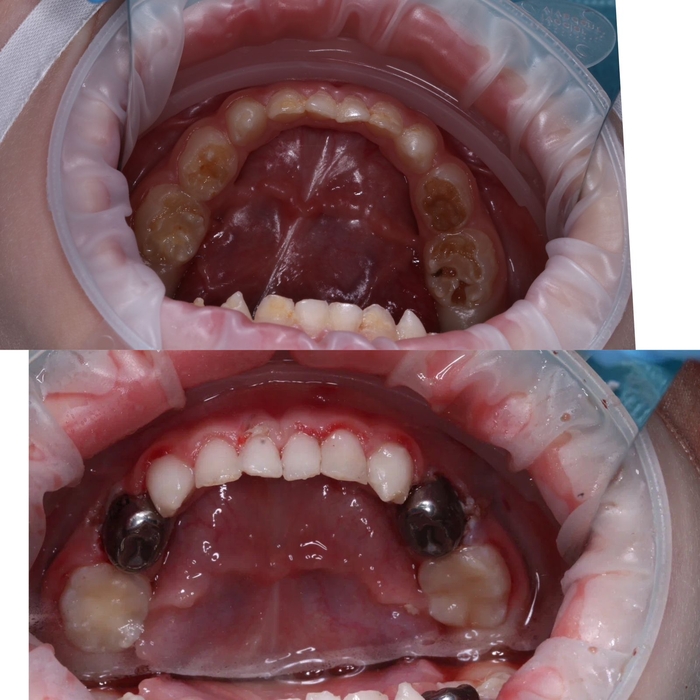

Настал тот день, когда мы пошли к платному стоматологу. Осмотр показал 11 кариесов и 7 пульпитов из 20 существующих зубов. Сделали снимки. Решили попробовать полечить зубы под маской (это когда ребенок через нос вдыхает специальный газ, который расслабляет его. Ребенок в сознании, он смотрит мультики на телеке на потолке кабинета, пока ему лечат зубы). Мой сын в кресло то сел, а вот маску надевать отказался. А если плакать и дышать ртом, она не сработает.

Было принято решение лечить зубы под наркозом (ребенка усыпляют, он спит несколько часов, пока ему лечат сразу все зубы). Был выдан огромный список анализов и консультаций врачей, а еще всякие прививки и справки от педиатра. Мы все собрали, был назначен день наркоза.

В день наркоза мы приехали, поговорили с анастезиологом, потом ребенка завели в операционную и усыпили при нас, а нас попросили выйти.

Муж просидел со мной в палате через стенку от операционной час, а потом уехал на работу. Я осталась. Действие шло 4,5 часа. Сына вынесли, он проснулся и увидел меня. Естественно плакал, жаловался на боль, и я тоже чуть не плакала от его опухшего лица и кровавого рта.

Мы приехали домой, он был вялый, все время лежал, поспал еще 2 часа, вечером поднялась температура. Утром небольшая температура все еще была, поэтому в садик мы его не повели.

Первые 3 дня были самыми тяжелыми, он хотел много всего есть, но не мог из за боли. Сегодня уже неделя с дня лечения, но зубы чистить и мазать десны мазью для заживления получается только через истерику. С едой стало лучше, он пока не ест только конкретно твердые вещи типа яблока.

Итог:

Установлены 4 металлические коронки на жевательных зубах и 4 керамические коронки на верхних передних зубах. Остальное пломбы. Сделала проф.чистка и фторирование, благодаря чему передние нижние зубы стали заметно белее.

Финансы:

- 7тыс за анализы и консультации врачей

- 37тыс за 4,5 часа наркоза

- 103тыс за первичную консультацию стоматолога, снимки всех зубов, консультацию анастезиолога и собственно само лечение и установка коронок

- 3тыс за лекарства для восстановления десен и импортные средства гигиены

Дело происходит в городе-миллионнике.

P. S. Я безмерно рада, что мы наконец это сделали и что кариес не дошел до зачатков коренных зубов. Меня восхищает, что нынешние дети имеют возможность лечить зубы с комфортом и без ударов по психике. Спасибо современным технологиям!